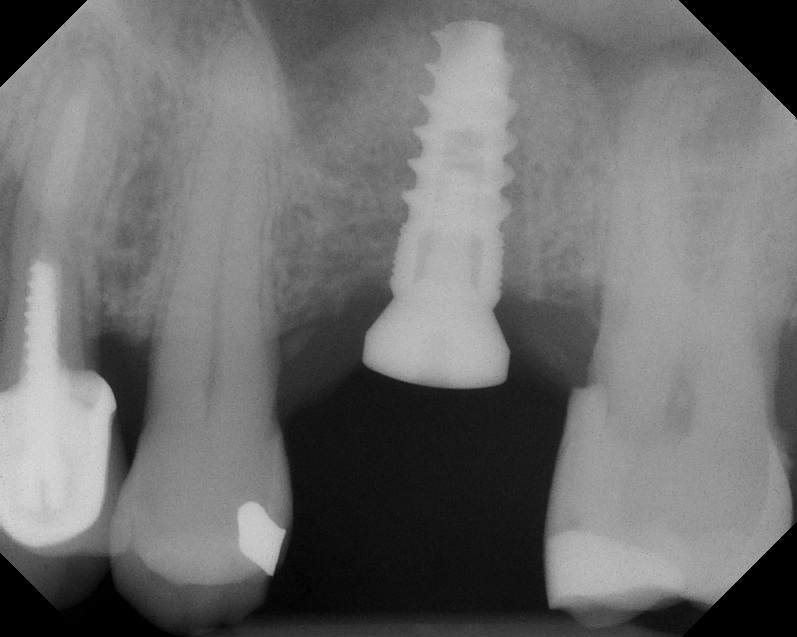

The implant is then delivered and should be well stabilized in the bone. If there is any mobility of the implant, it can either be placed a little deeper (if there is enough native bone) or the implant can be removed and the procedure aborted, in which case it would be a two-stage procedure. This should rarely occur with the tapered designed implant, even with only 2 mm of native bone. Using a bone-level platform-shifting implant (or a tissue-level designed implant) is critical, as the hard and soft tissue will establish a biologic width. If an external hex type of implant is used and the shoulder is placed at the bone level, an expected bone loss of 1.5 mm to 2 mm will occur.24 Figure 10 shows proper bone-level implant depth placement with a platform-shifting design. In this case, a 3-mm healing abutment was placed at the time of surgery to avoid a secondary uncovering surgery, but an implant-level healing abutment could have been placed instead. As can be seen, there was only about 2 mm to 3 mm of native bone height. The membrane was raised about 8 mm to 9 mm. Comparing the radiograph on the day of surgery (Figure 10) to the 6-month postoperative radiograph (Figure 11) shows no loss of native bone, as well as the positive change in appearance of the grafted bone. The 3.5-month CBCT scan (Figure 12) shows good healing of the bone with no coronal bone loss. With minimal native bone present, as in this case, the use of a non-platform-shifting or non-tissue-level implant design could be problematic. After 1.5 mm to 2 mm of crestal bone loss, an external hex designed implant could develop instability with possible implant failure. If a non-tapered implant is used and bone loss occurs during healing, migration of the implant into the sinus could potentially occur. The surgeon can use either a healing abutment or implant-level closure screw over the implant shoulder. With patients who tend to use their tongues to explore or play with the area, or if the area is under a removable partial denture, a closure screw is recommended.

Radiograph of implant N o. 3 and sinus augmentation, day of placement. There is about 2 mm to 3 mm of native bone, and the sinus has been raised about 8 mm to 9 mm.

Fig. 10

A 7-month postoperative radiograph of the restored implant No. 3.

Fig. 11

CBCT scan (Kodak 9000D) showing 3.5-month postoperative of implant No. 3 in place. Note homogeneous appearance of the bone.

Fig. 12